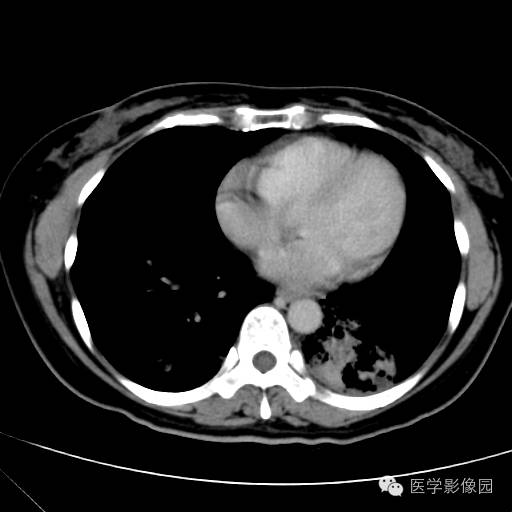

肺叶实变性支气管肺泡癌1例CT影像表现